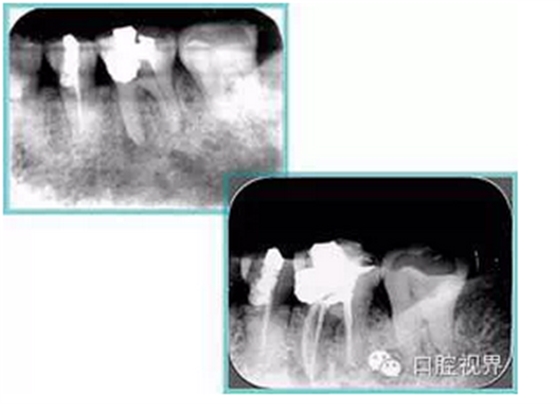

共有 4 張 X 線片,分別是術前、診斷絲 、主牙膠尖確認、術后。

( 1 )術前:術前 X 線片用來了解牙齒的大概情況。術前預期為多根牙時 X 線片應偏頭拍攝。

( 2 )診斷絲:根據(jù)術前 X 線片進行開髓、根管的初步預備后,需要插入診斷絲,用來指示工作器械位置。常用 10 號或 15 號擴大器作為診斷絲插入牙髓腔。

( 3 )主牙膠尖確認:通過術前預期和診斷絲診斷,明確工作長度、牙根走向,進行根管預備。之后應進行主牙膠尖(中銼)確認,已明確根管是否適合充填。

( 4 )術后:觀察治療效果。

左圖為根管充填術后 X 線片。圖中可見,根管充填較好。右下圖有白色小點,為側方加壓導致糊劑擠出所致,表明根管充填比較致密。

多根牙時候需進行偏移投照,正位投照無法說明具體哪根牙根管充填效果。